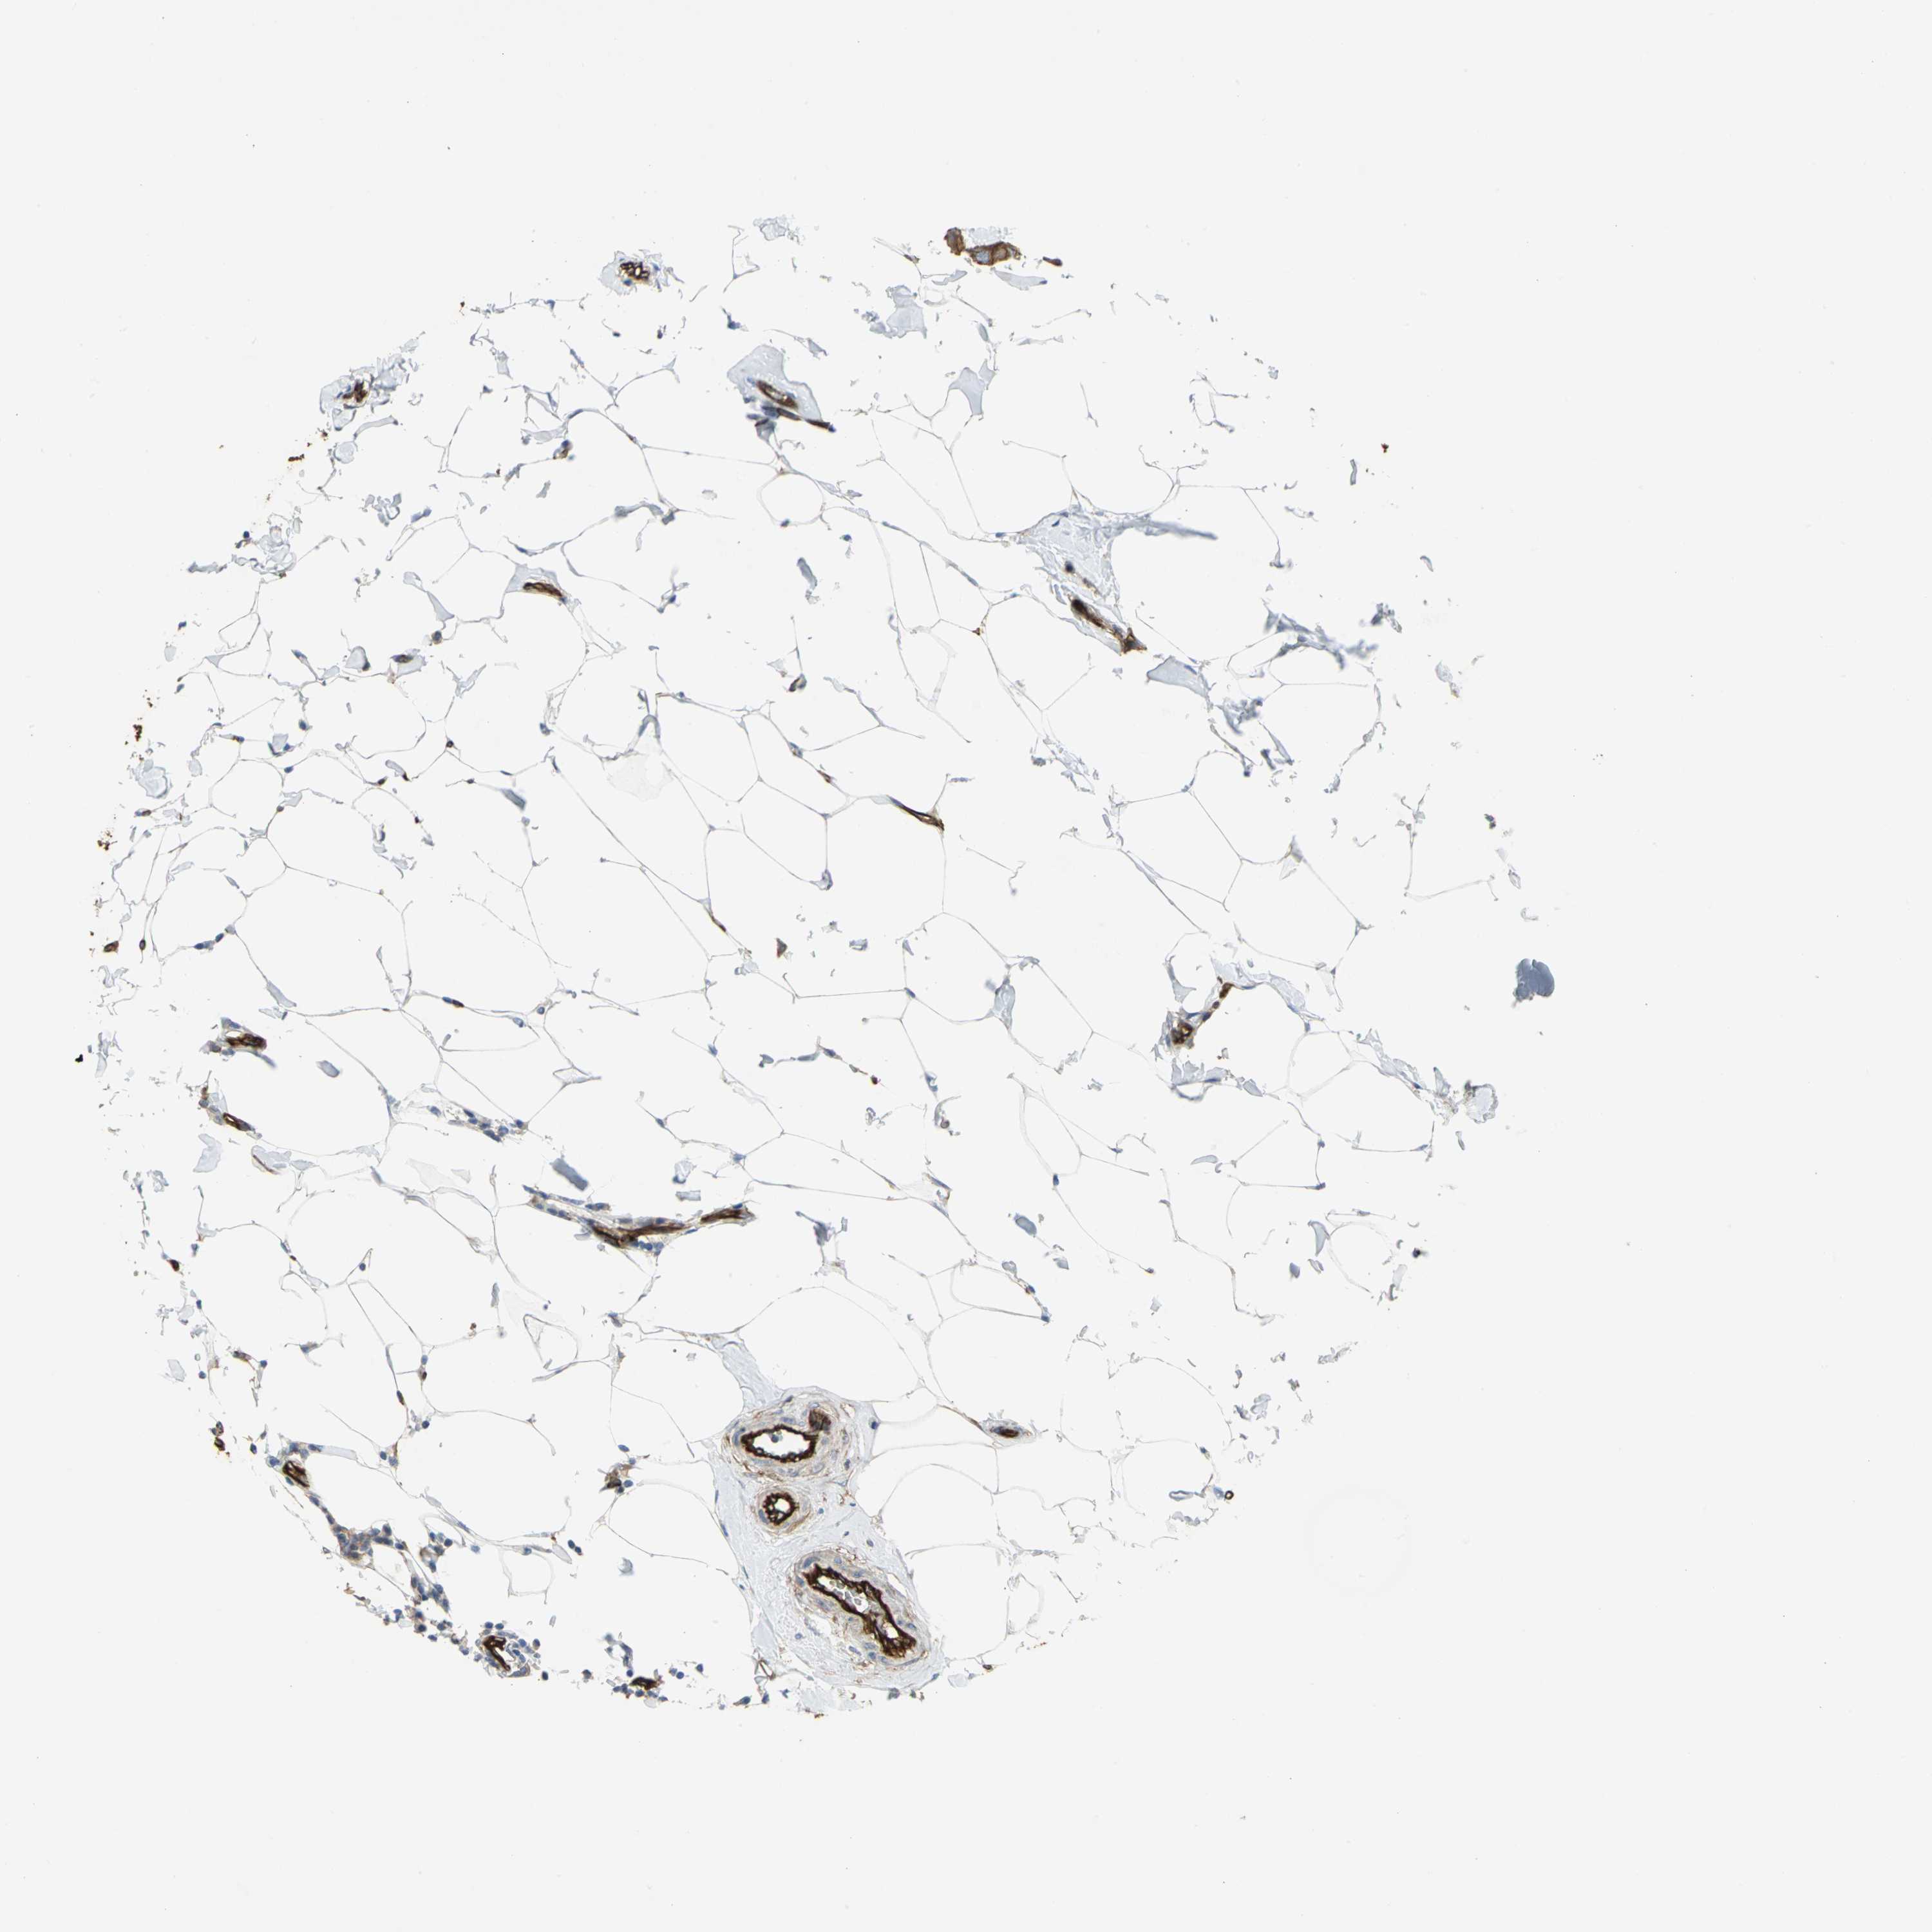

CANCER BREAST CANCER Show tissue menu

BRCA TCGA BRCA VALIDATION PROTEIN EXPRESSION

ANTIBODIES

AND

VALIDATION